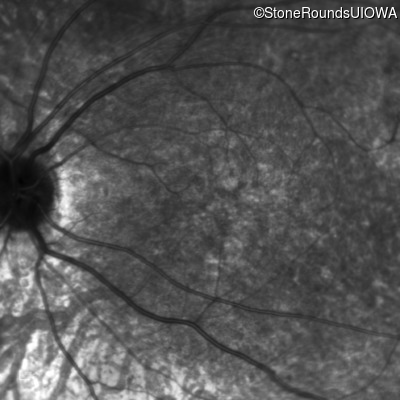

AR Stargardt Disease (IIA)

Age at visit: 8 years

This 8 year old girl had normal vision until age 6 when she failed a school vision screening. That year, she was able to play softball well, but this year she often loses sight of the ball and is often hit by it.

AR Stargardt Disease ABCA4 IVS38-10T>C IVS38-10T>C AR